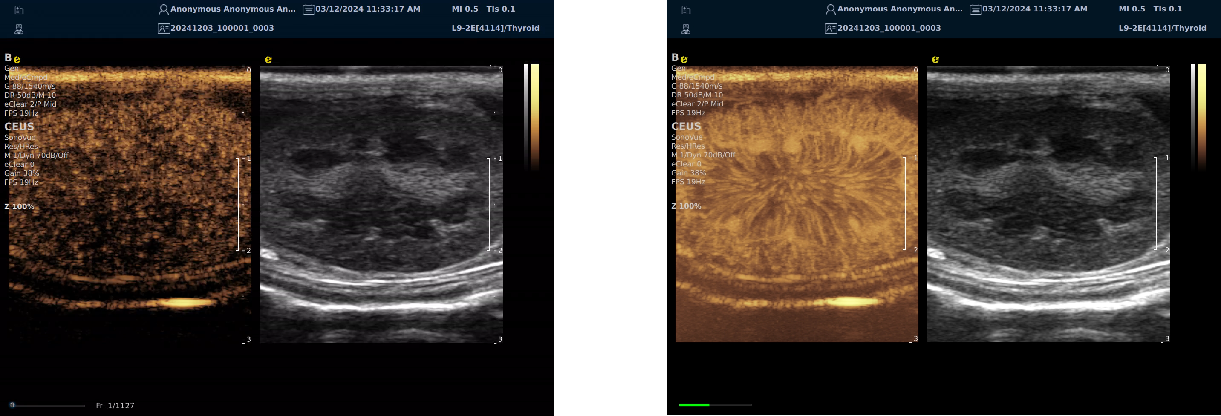

超声造影

医生可以更准确地识别和评估肿瘤、炎症、血栓等病理变化,从而提高诊断的准确性和可靠性

可以实现实时监测,特别是在手术过程中,帮助医生即时评估治疗效果和发现潜在问题

可以提供关于血流动力学的重要信息,例如评估血管的通畅性、血流速度和分布情况,这对于诊断动脉硬化、栓塞等疾病非常有帮助